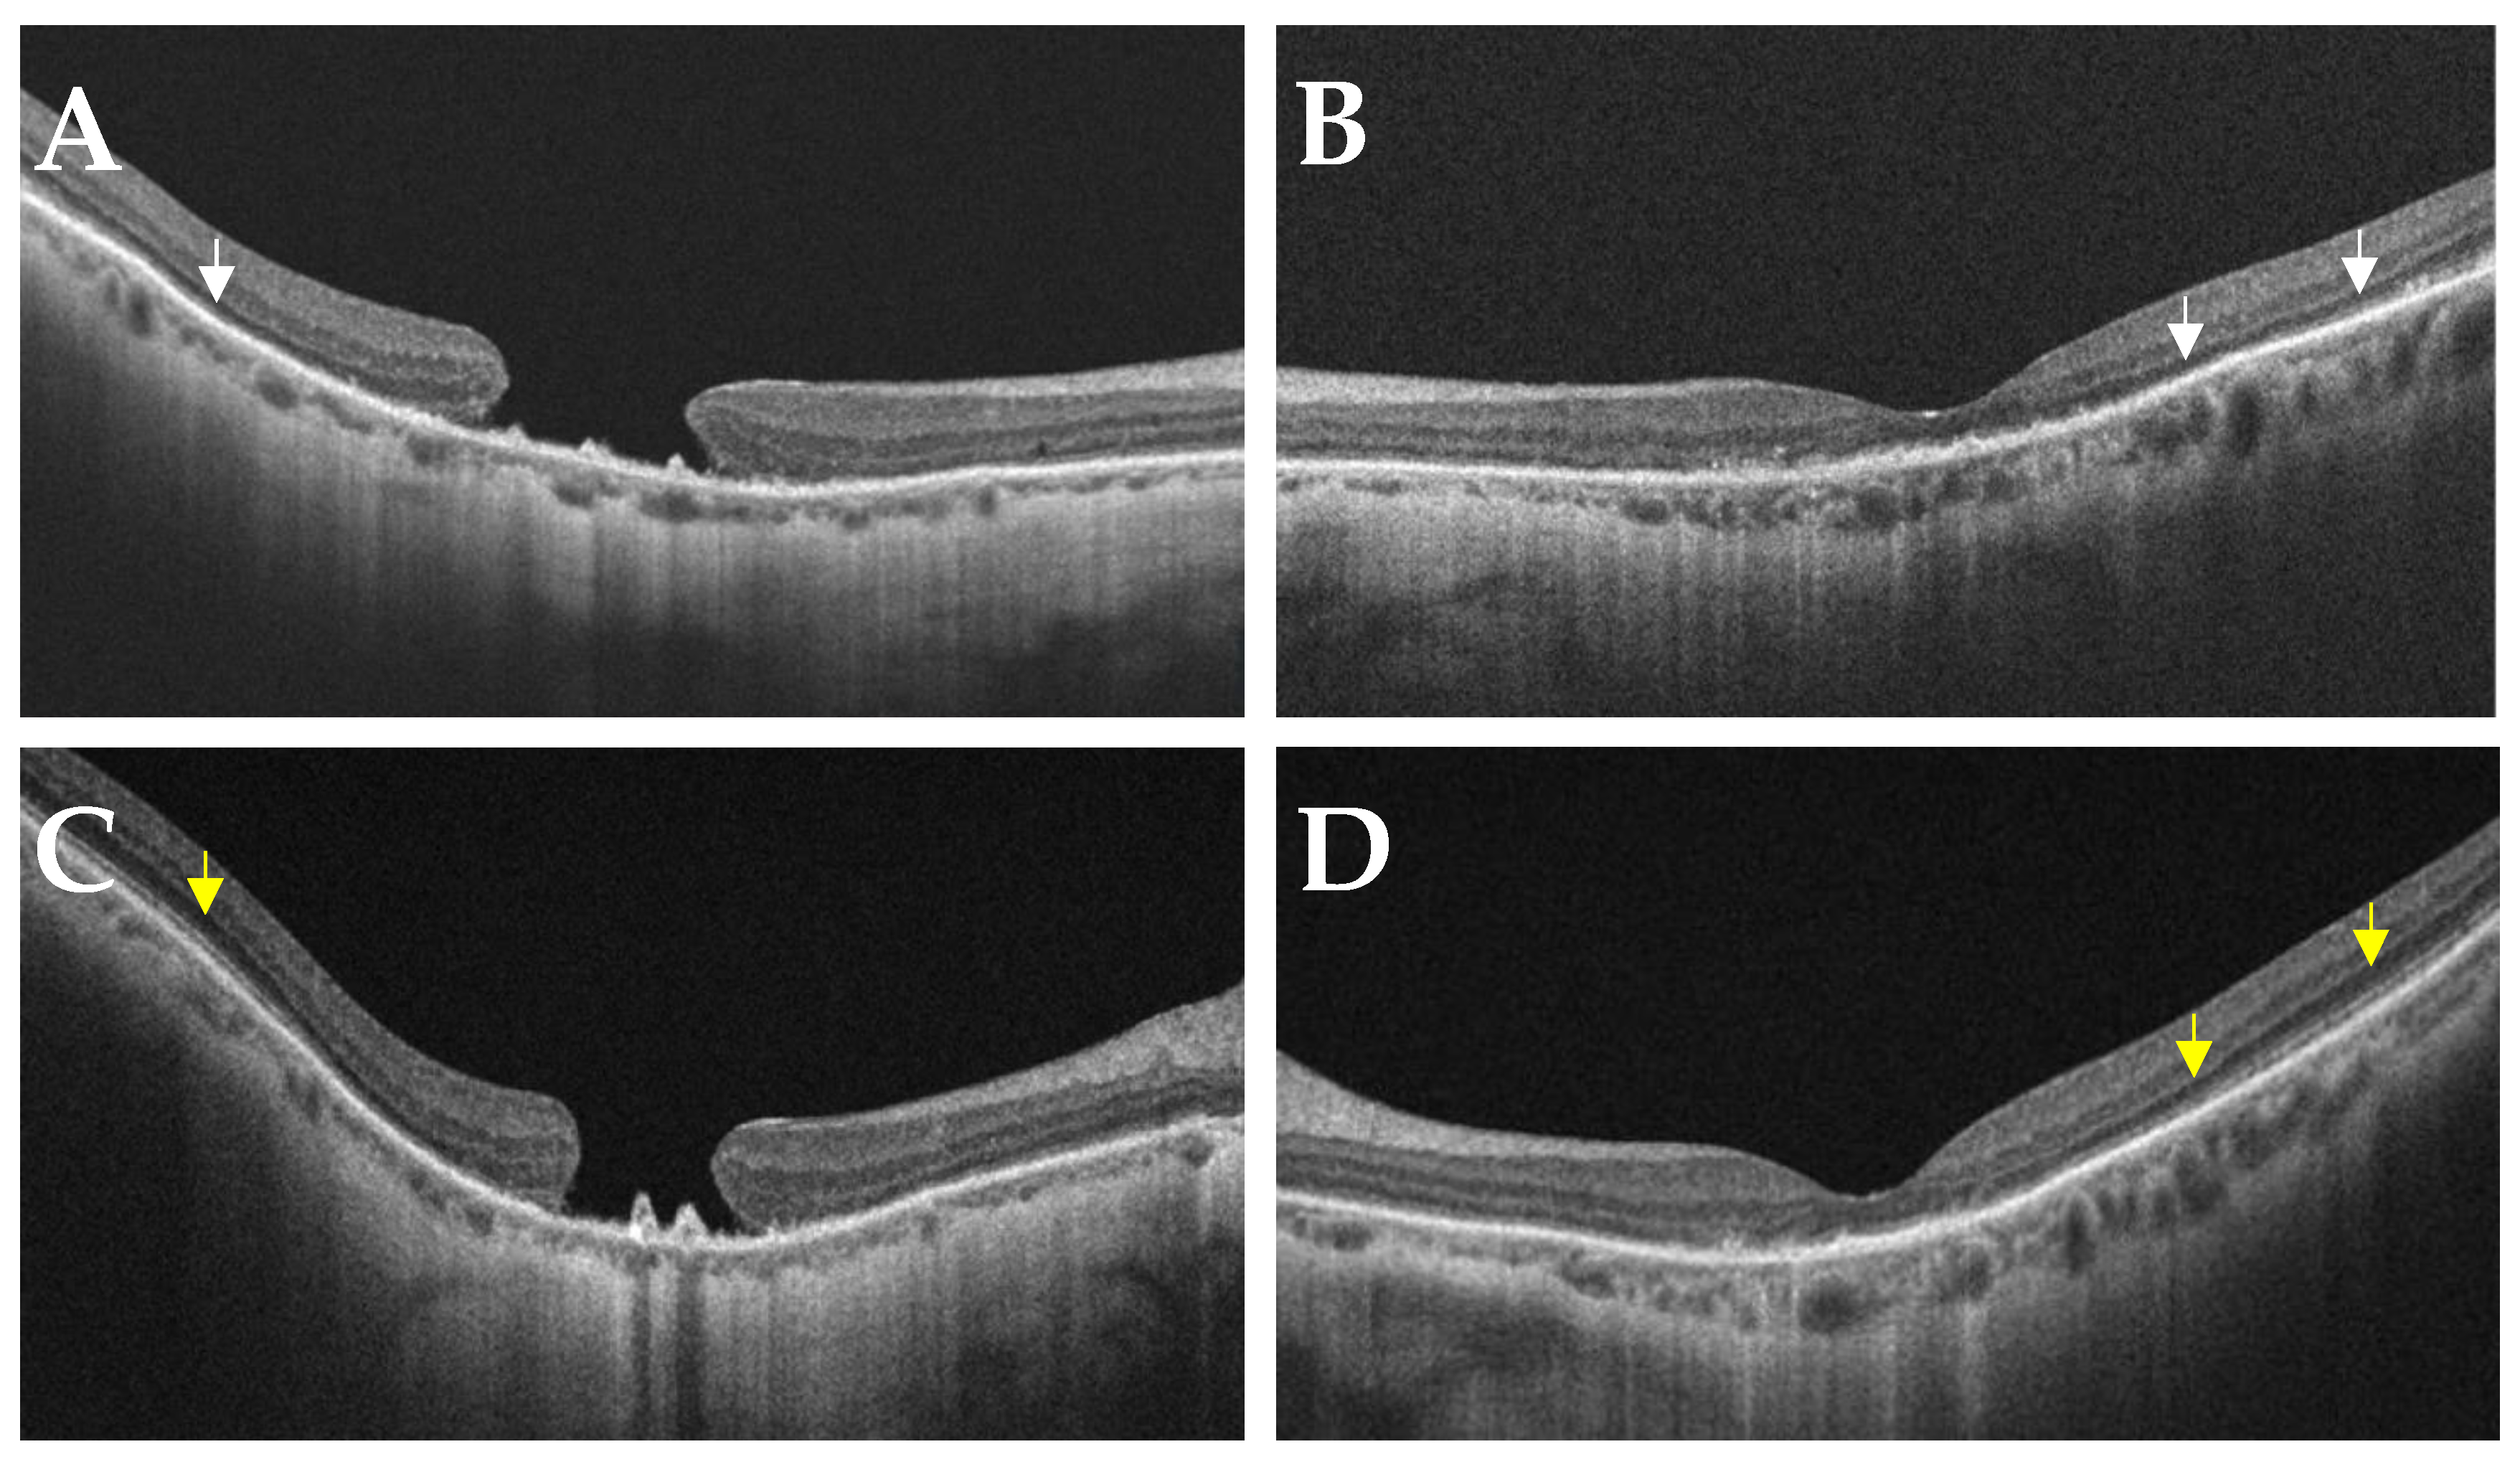

- Case 1:

- Case 2: